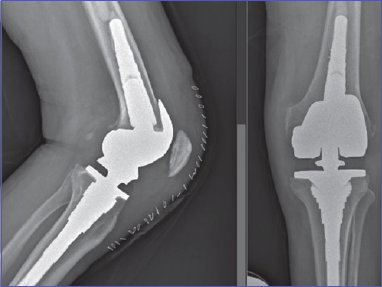

On inspection, the knee was swollen, an anatomical deformity with 90° knee flexion was noted. The patient did not complain of paresthesia or sensory deficits. The limb was warm and with palpable pulses. X-ray exam showed a PL knee dislocation (Fig. 1). Closed reduction and immobilization with posterior brace were performed, under conscious sedation, in the emergency department. Neurovascular status was closely monitored. Angio-CT scan was performed to exclude vascular injuries (Fig. 2). The patient was hospitalized. Neurovascular status, skin condition and clinical parameters were strictly monitored. The knee was unstable with persistent PL subluxation, worsened by dyskinesias, and both varus and valgus instability. The lesion was classified as a grade IV KD of Knee Dislocation Classification System. A staged multi-ligament reconstruction in two steps was planned: acute reparation of MCL and LCL and a staged reconstruction of both ACL and PCL. A neurologist was consulted to optimize the patient’s therapy with the aim of reducing the risk of recurrence. After 3 days we performed an acute surgical reparation of both the MCL and LCL. A 30° locked knee brace was placed. Postoperative X-rays exam (Fig. 3) showed perfect knee reduction. On the fifth postoperative day the patient was discharged with home care and an outpatient controls program. We planned to unlock the brace after 25 days, check the ligament status and then perform a knee MRI in order to plan an ACL-LCL reconstruction within 2 months. After 25 days, patient came to the outpatient department to unlock the brace. We noticed a relapse of PL subluxation with varus-valgus instability and failure of the MC and LCL reparation. The main causes of failure were the persistent and violent dyskinesias, due to Parkinson disease. In this context, plan a staged reconstruction would have been at high risk of another ligament failure. Thus, we talked with patient, and changed the strategy. Three months after the injury the patient was hospitalized and underwent, in general anesthesia, a total knee replacement with a hinged prosthesis (Fig. 4). We choose a hinged prosthesis to make the implant as stable as possible to resist dyskinesias. Postoperative anemia was observed, requiring the transfusion of 2 concentrated red blood cell units. No other postoperative complication was observed. From the day after surgery the patient started active and passive mobilization of the knee and a re-education protocol with full weight bearing. The patient was discharged on the 7th postoperative day to continue rehabilitation. Clinical and radiographic controls were performed at 3, 6, 12 months and then annual follow-up. At the last follow-up (3 years) the patient was walking without crutches, with full ROM, no pain and the same level of activity as before the injury (Fig. 5).

Figure 1.Knee X Ray at emergency department.